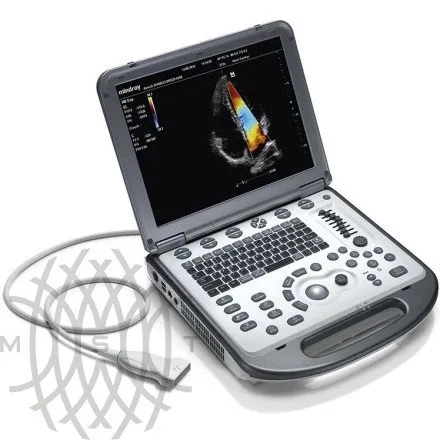

УЗИ аппарат Mindray M6 портативный

Характеристики

- M6 основной блок

- 15" монитор высокого разрешения

- Режимы сканирования:B/M/CFM/PDI/Направленный PDI/PW/Цветной M-режим

- Импульсно-волновой допплер PW (включая режим высокой частоты повторения импульсов HPRF)

- iBeam™ - многолучевое сложносоставное сканирование

- iClear™ - адаптивный алгоритм подавления зернистости

- PSH™ - Гармоника с фазовой инверсией

- iTouch™ - автоматическая оптимизация изображений

- iZoom™ - увеличение изображения во весь экран

- HR Flow - Режим отображения кровотока с высоким пространственным разрешением

- iScanhelper -Встроенный атлас ультразвуковых исследований

- 1T твердотельный жесткий диск и База данных пациентов iStation™

- Разъем S-Video и 2.0 USB порты

- Блок питания и литий-ионная батарея

- Кейс (чемодан) для транспортировки